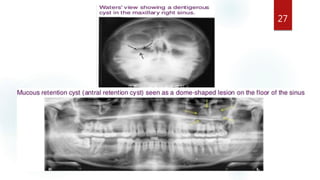

ODONTOGENIC CYST LESIONS 26

Odontogenic cysts

are the most common

group of extrinsic

lesions that encroach

on the maxillary

sinuses.

• The cyst enlarges ,the

sinus decrease in size

• The result is radioopaque

line between

the cyst and the air

space of the sinus.

27